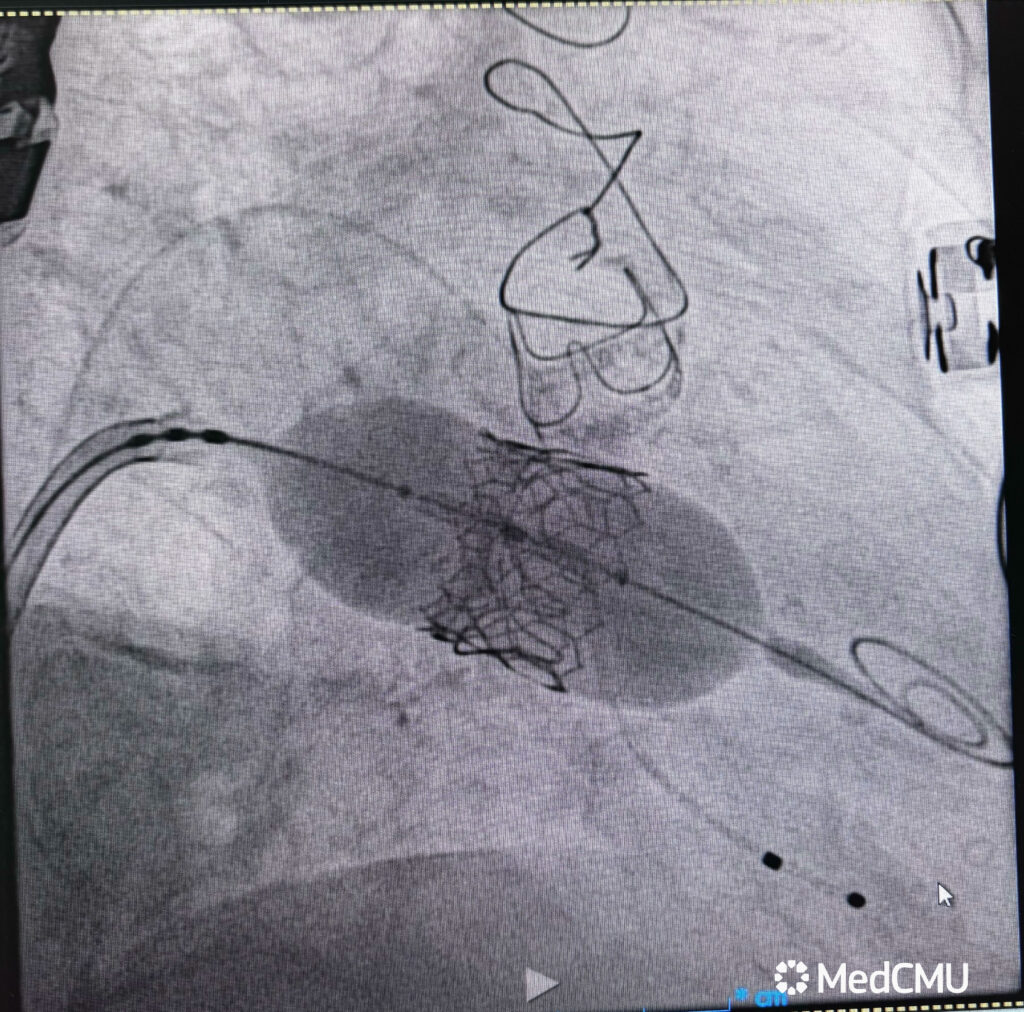

คณะแพทยศาสตร์ มหาวิทยาลัยเชียงใหม่ ประสบความสำเร็จในการรักษาผู้ป่วยหญิงไทย วัย 83 ปี ด้วยเทคนิคการเปลี่ยนลิ้นหัวใจไมตรัลเทียมตัวใหม่ แทนที่ตัวเก่าที่เสื่อมสภาพ ผ่านทางสายสวน โดยเทคนิคการตัดลิ้นหัวใจอันเดิม (LAMPOON – Laceration of the Anterior Mitral Leaflet to Prevent Outflow Obstruction) ถือเป็นรายแรกในระดับภูมิภาคของประเทศไทย ที่มีการทำหัตถการดังกล่าว และเป็นความก้าวหน้าสำคัญในการดูแลผู้ป่วยโรคหัวใจซับซ้อน

อ.พญ.ทรรศลักษณ์ ทองหงษ์ เปิดเผยว่า “เทคนิค LAMPOON ถือเป็นก้าวใหม่ของหัตถการในการรักษาภาวะแทรกซ้อนของการใส่ลิ้นหัวใจเทียม เนื่องจากต้องอาศัยความแม่นยำสูงในการเลาะพังผืดและกรีดลิ้นหัวใจเดิม เพื่อป้องกันการอุดกั้นทางออกของหัวใจ การทำหัตถการนี้ต่างจากการเปลี่ยนลิ้นหัวใจด้วยสายสวนแบบทั่วไป เพราะผู้ป่วยมีลิ้นหัวใจเทียมชนิดเก่าอยู่แล้วซึ่งเสื่อมสภาพจนทำให้เกิดภาวะแทรกซ้อน ซึ่งหากเป็นวิธีการเดิม ผู้ป่วยจำเป็นต้องรับการผ่าตัดเปิดทรวงอกซ้ำซึ่งมีความเสี่ยงสูงมาก แต่ในครั้งนี้ ทีมแพทย์สามารถทำได้สำเร็จ และผู้ป่วยฟื้นตัวได้โดยไม่ต้องเปิดทรวงอก ถือเป็นก้าวสำคัญในการดูแลผู้ป่วยหัวใจที่ซับซ้อน”

รศ.นพ.นเรนทร์ โชติรสนิรมิต คณบดีคณะแพทยศาสตร์ มหาวิทยาลัยเชียงใหม่ กล่าวว่า “ผู้ป่วยรายนี้มีความซับซ้อนทางโรคหัวใจสูง ทั้งจากการผ่าตัดหัวใจมาก่อนและภาวะเสื่อมของลิ้นหัวใจเทียมเดิม การบูรณาการความรู้จากทีมแพทย์ผู้เชี่ยวชาญในหลายแขนงของคณะแพทยศาสตร์ มช. รวมถึงเครือข่ายแพทย์จากไต้หวัน ทำให้สามารถใช้เทคนิค LAMPOON ผ่านสายสวนแทนการผ่าตัดเปิดอกได้สำเร็จลุล่วงไปด้วยดี ซึ่งความสำเร็จนี้ แสดงให้เห็นถึงศักยภาพในการพัฒนานวัตกรรมการรักษาโรคหัวใจขั้นสูงในประเทศไทย ไม่เพียงแต่จะช่วยชีวิตผู้ป่วยได้ แต่ยังเป็นประโยชน์ต่อการพัฒนาการคณะแพทยศาสตร์ มช. และวงการแพทย์ไทยในอนาคต”